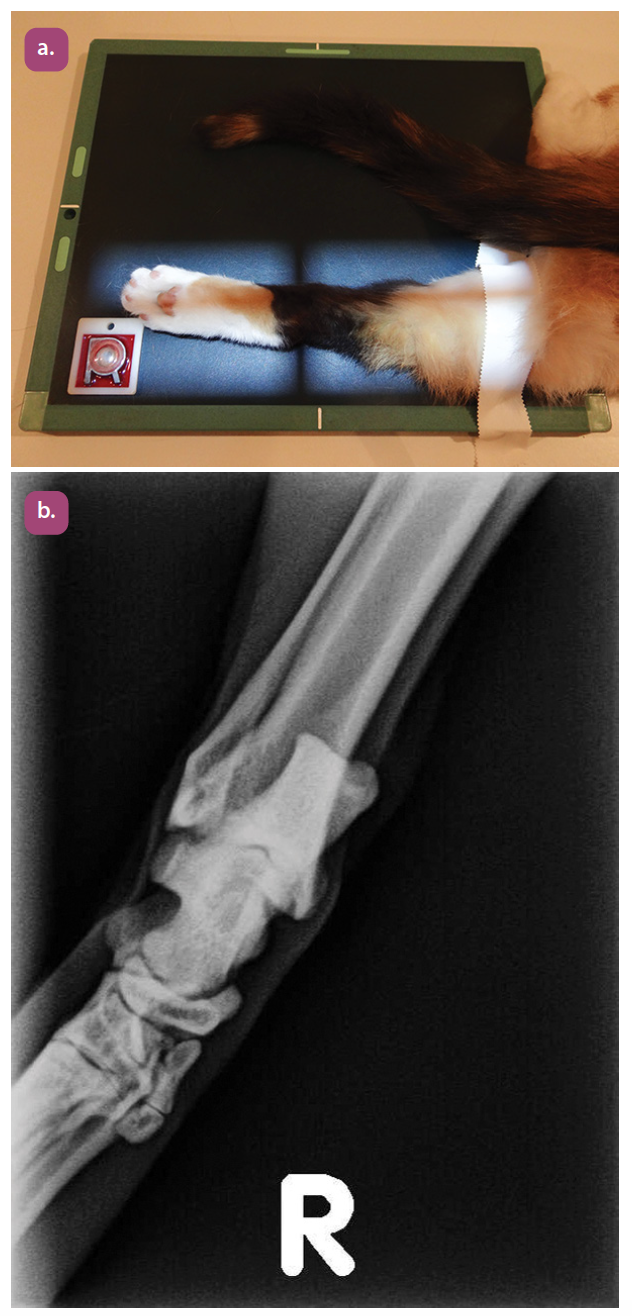

mediolateral projection of the radius and ulna

craniocaudal projection of the radius and ulna